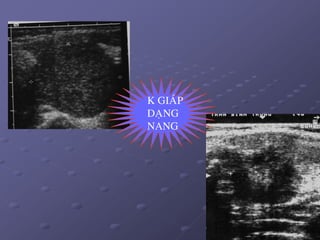

K GIAÙP

DAÏNG

NANG

 86,7% laø nhaân ñaëc echo keùm, khi lôùn hôn 1 cm nhaân trôû

neân khoâng ñoàng nhaát, giôùi haïn khoâng roõ, 50% coù vi voâi hoùa,

ít thaáy ñöôïc hình daïng nhuù trong nang.